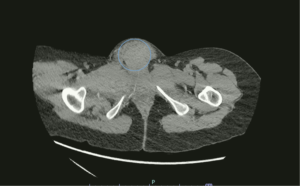

Vulvar Hematoma. CT Axial, Annotated. JETem 2024

Vulvar Hematoma. CT Axial Annotated. JETem 2024